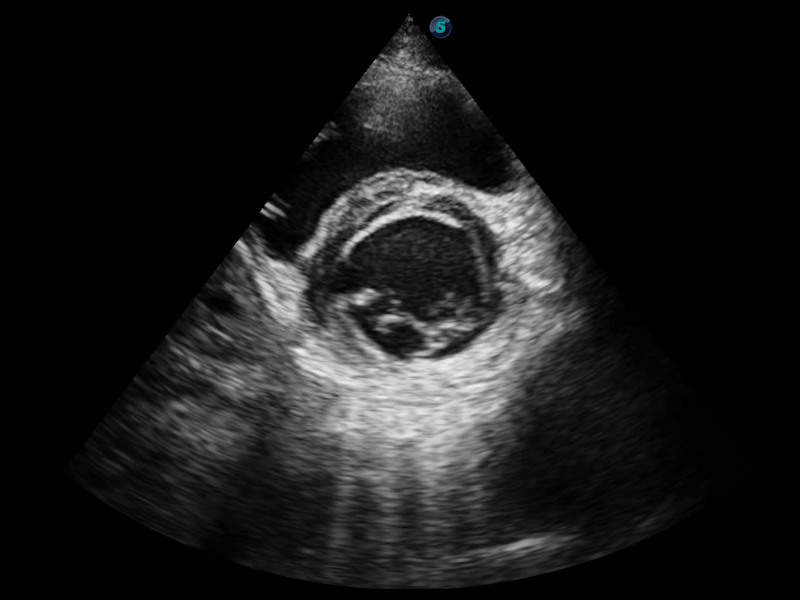

S-Fetus 产科扫查助手

S-Fetus基于大数据深度学习算法,能够帮助您在产前筛查过程中智能识别胎儿标准切面、自动测量并录入报告。一个按键,即可智能、精准、高效地获取胎儿生理指标,极大简化您的产科检查操作。

临床图像